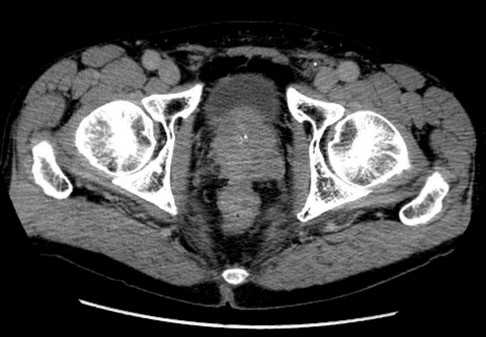

Пациент К., 1965 года рождения, при плановом обследовании в поликлинике по месту жительства в марте 2017 г. выявлено повышение уровня ПСА до 6,5 нг/мл, в связи с чем в ГКБ № 29 Москвы выполнена трансректальная биопсия предстательной железы, гистологически верифицирована ацинарная аденокарцинома 6 (3+3) баллов по Глисону. Больной самостоятельно обратился в МНИОИ им. П.А. Герцена. При пересмотре стекол препаратов биопсии предстательной железы в условиях патоморфологического отделения МНИОИ им. П.А. Герцена на фоне гиперплазии предстательной железы с очагами атрофии в 5 фрагментах из 12 выявлен рост ацинарной аденокарциномы 7 (4+3) баллов по Глисону, занимающей до 100% площади столбиков. По данным УЗИ и МРТ малого таза, предстательная железа размером 42×34×30 мм, объемом до 30 см 3 (рис. 3). Рис. 3. Магнитно-резонансная томограмма малого таза.

В периферической зоне правой доли определяется очаг раннего накопления контрастного препарата 13×10 мм без инвазии в капсулу железы и семенные пузырьки. В полости малого таза измененные лимфатические узлы не выявлены. При пальцевом ректальном исследовании предстательная железа не увеличена в размере, не деформирована, эластической консистенции, без пальпируемых узловых образований, междолевая бороздка сглажена. Слизистая оболочка прямой кишки над железой подвижна. Другой очаговой опухолевой патологии при комплексном обследовании не выявлено. На основании обследования установлен клинический диагноз: рак предстательной железы I стадии сТ2аN0M0. Больной обсужден на консилиуме с участием хирурга, химиотерапевта, лучевого терапевта и онколога: учитывая размер, локализацию и распространенность опухолевого процесса, отсутствие отдаленных и регионарных метастазов, рекомендовано хирургическое лечение. 10.04.17 больному выполнено хирургическое лечение в объеме радикальной простатэктомии, расширенной тазовой лимаденэктомии. Послеоперационный период протекал гладко, без особенностей. При контрольном УЗИ органов малого таза и вен нижних конечностей от 17.04.17 в полости малого таза объемных образований не выявлено. Поверхностные и глубокие вены обеих конечностей проходимы, без тромбоза и флебита. По данным цистографии от 17.04.17, подтверждена герметичность везикоуретрального анастомоза, в связи с чем 19.04.17 уретральный катетер удален, восстановлено самостоятельное мочеиспускание. Проведены антибактериальная, инфузионная, симптоматическая терапия и профилактика тромбоэмболических осложнений с положительным эффектом. Послеоперационная рана зажила первичным натяжением.